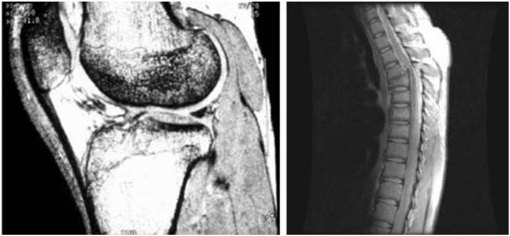

- 주요 응용분야: 의학(MRI: magnetic resonance image), 천문학

인체의 MRI 무릎, 척추